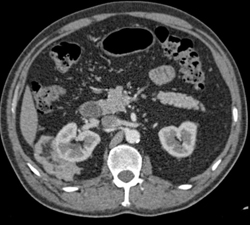

Dilated Calyces in Left Kidney With Ureteropelvic Junction (UPJ) Due to Crossing Vessel